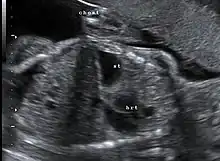

Congenital diaphragmatic hernia: coronal obstetric ultrasound (head to right of image, thorax centre, abdomen left) shows the stomach and heart both within the thorax.

This condition can often be diagnosed before birth and fetal intervention can sometimes help, depending on the severity of the condition.[8] Infants born with diaphragmatic hernia experience respiratory failure due to both pulmonary hypertension and pulmonary hypoplasia. The first condition is a restriction of blood flow through the lungs thought to be caused by defects in the lung. Pulmonary hypoplasia or decreased lung volume is directly related to the abdominal organs presence in the chest cavity which causes the lungs to be severely undersized, especially on the side of the hernia.